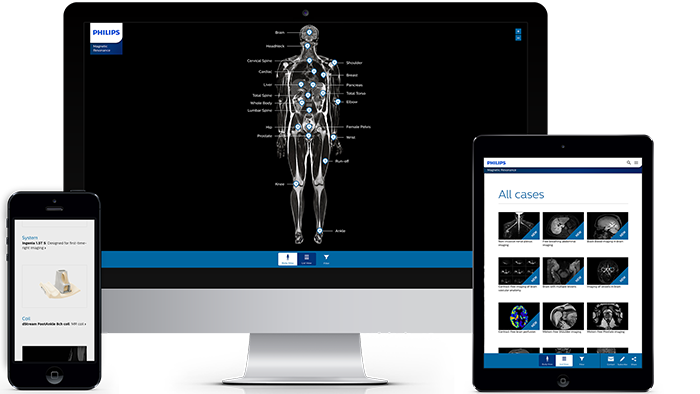

Mapa del cuerpo con el resonador magnético

Casos clínicos de casi todas las anatomías Explore más de 100 casos clínicos de sus colegas en todo el mundo que muestran cómo la tecnología digital de resonancia magnética de Philips fortalece sus necesidades de imágenes.